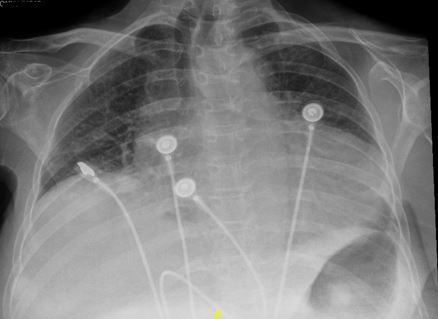

A 55 yo F with a history of untreated hypothyroidism presents to the ED with fatigue, SOB, abdominal distension and lower extremity edema. Her symptoms have been progressively worsening over the last month. Exam is significant for diminished heart sounds, clear lungs and abdominal ascites. EKG shows low voltage throughout. A CXR and bedside US are done and shown below. What's the diagnosis? (scroll down for answer)

Answer: Pericardial Effusion

- CXR shows "boot shaped heart"